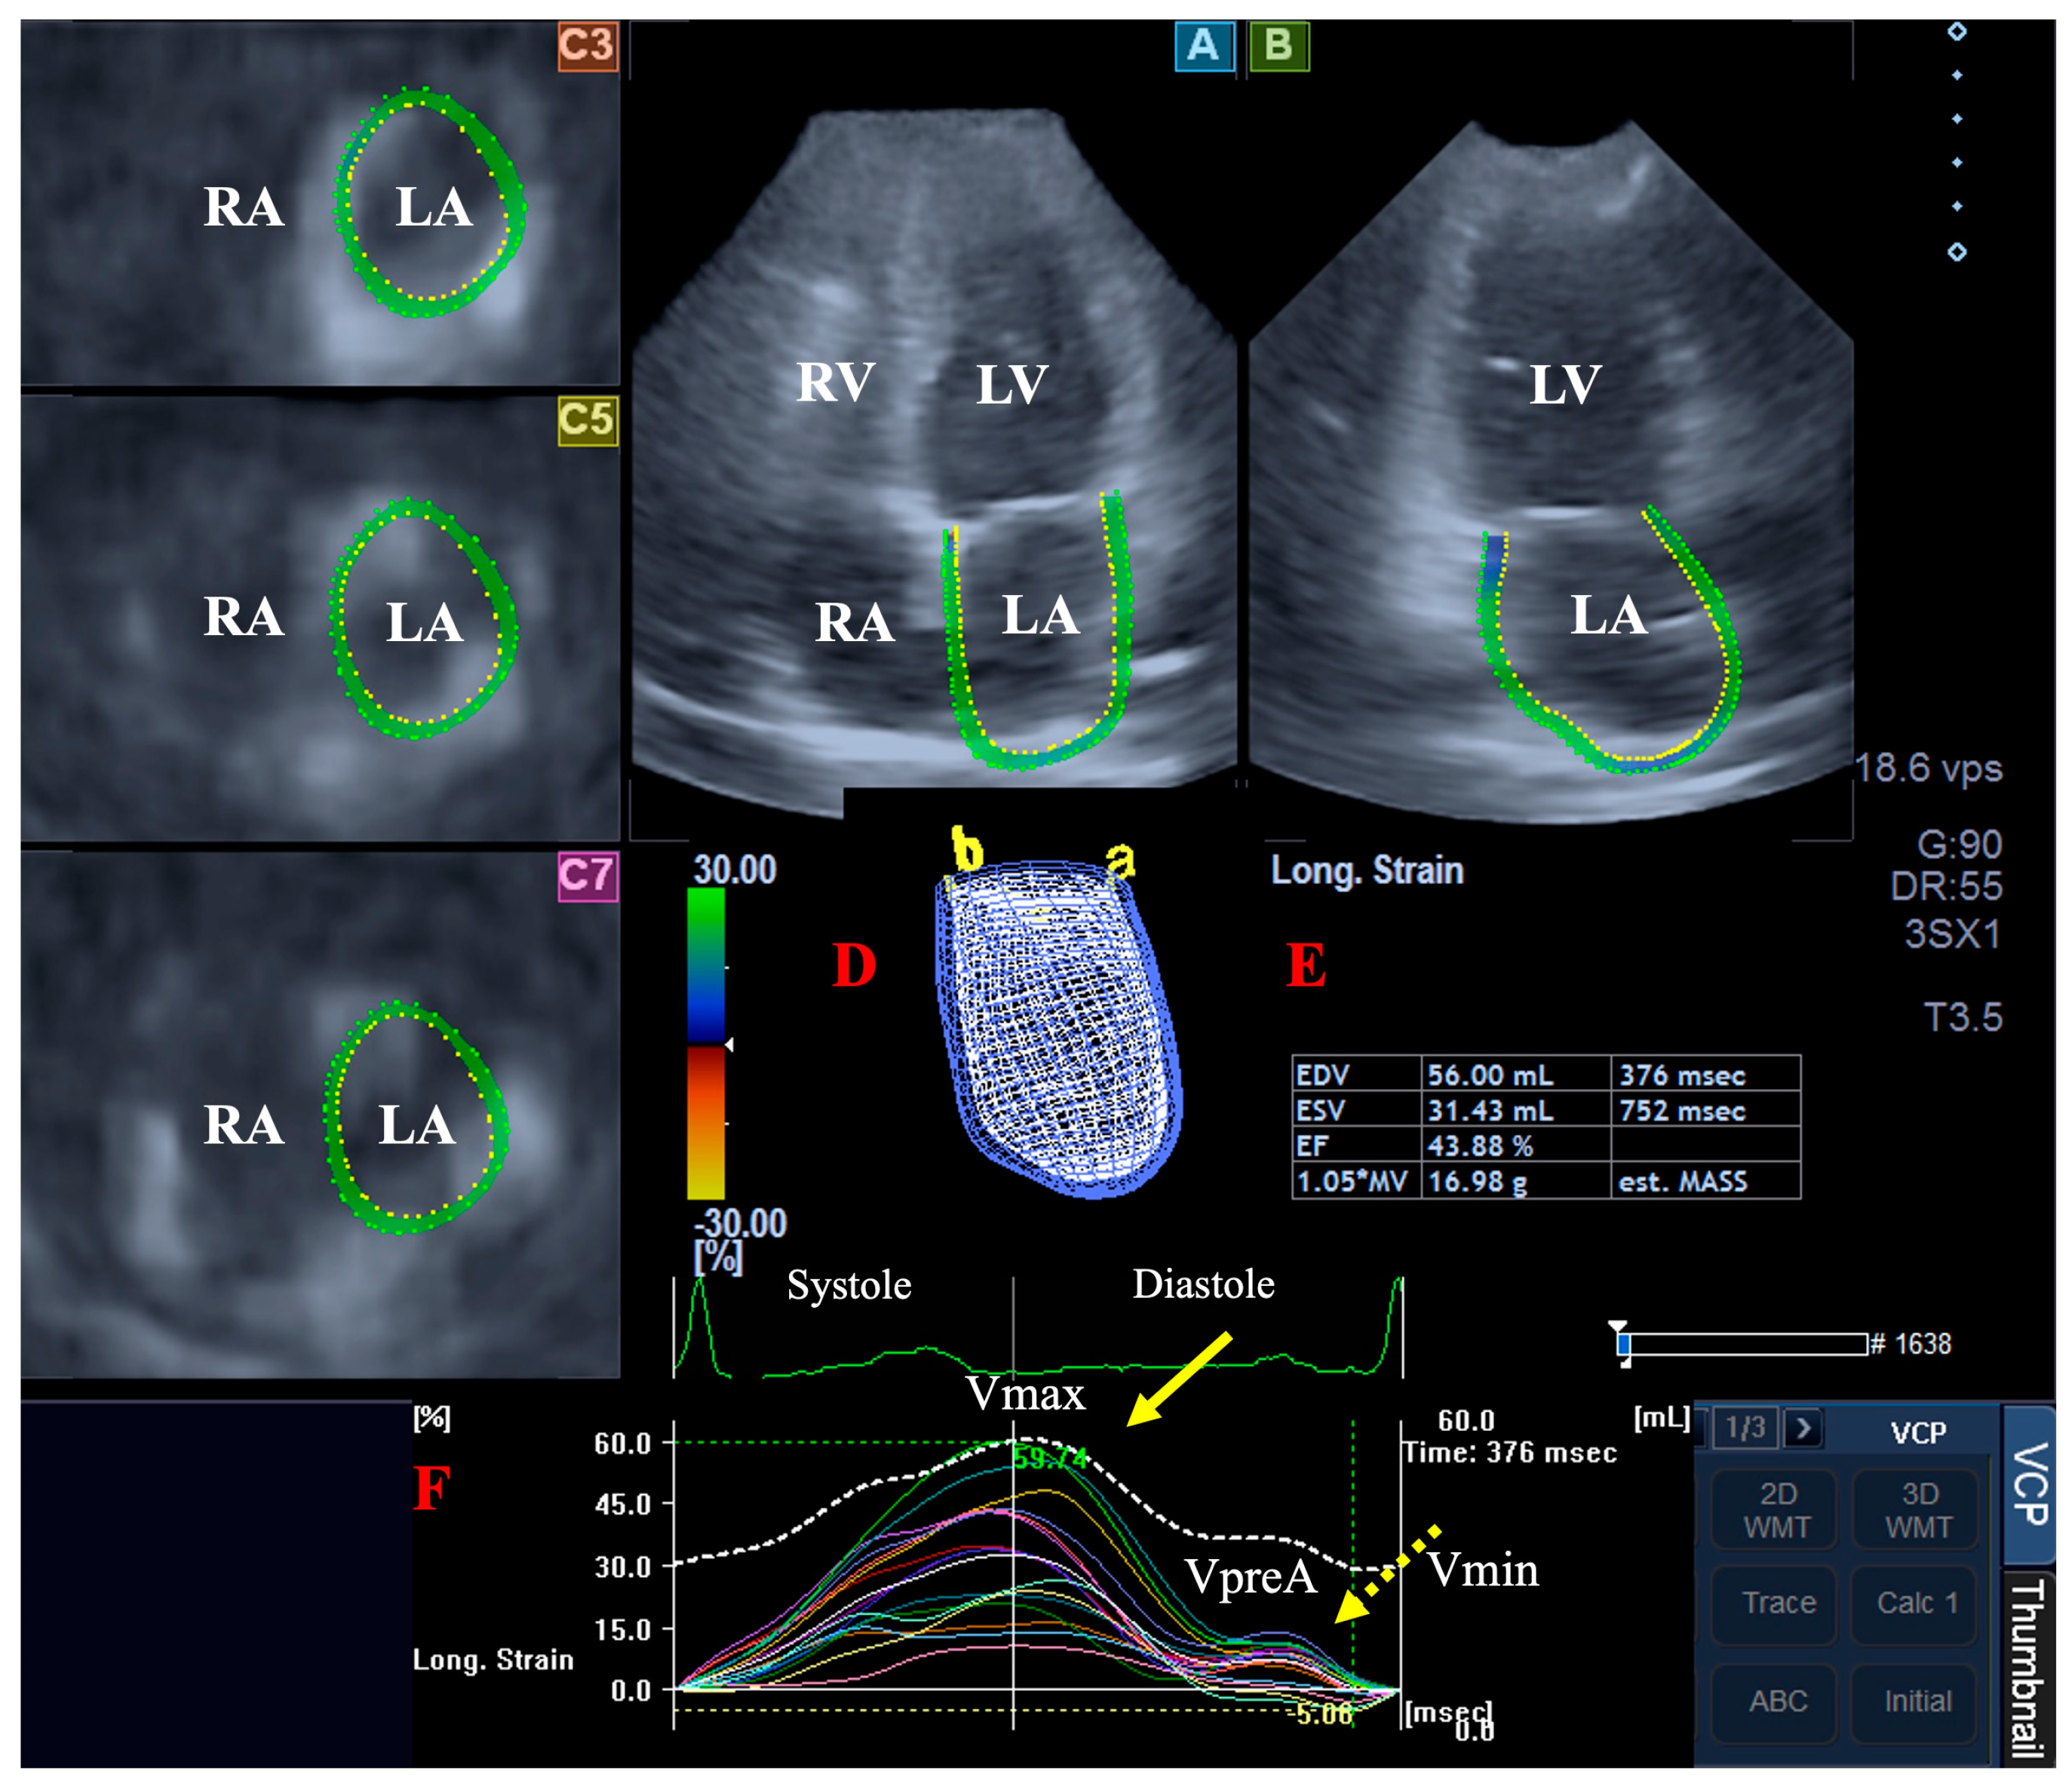

- End-systolic maximum LA volume (Vmax, before mitral valve opening);

- Early diastolic LA volume before atrial contraction (VpreA, at the time of the P-wave on the ECG);

- End-diastolic minimum LA volume (Vmin, before mitral valve closure).